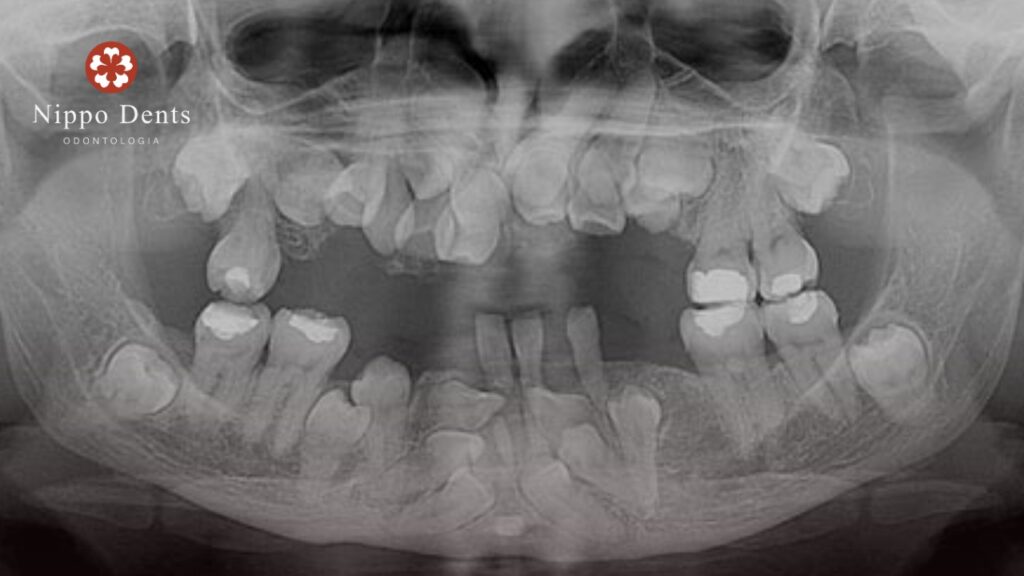

Sinais dentários — o ponto de maior impacto clínico

- Atraso significativo na queda dos dentes de leite

- Dentes permanentes que não erupcionam

- Dentes supranumerários (excesso de dentes)

- Mordida aberta ou desalinhada

- Dentes inclusos que exigem tracionamento

“É muito comum que os primeiros sinais apareçam na dentição. Quando percebemos atraso importante ou um número muito acima do normal de dentes, a investigação deve ser iniciada.” 🦷

2. Exames de imagem

- Radiografias panorâmicas

- Radiografias periapicais

- Tomografia computadorizada 3D (fundamental para planejamento)